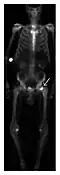

Figure 14: Subcapital insufficiency fracture in a 55-year-old man with a left hip pain without a history of trauma. Anteroposterior and Lauenstein view radiographs centered on the left hip do not show an obvious fracture line, but mild acetabular osteophytosis was noted consistent with hip osteoarthritis (not shown). (a) Coronal T1-weighted MRI shows a linear low-signal band through the femoral neck corresponding to a fracture line (arrowheads). (b) Bone scintigraphy shows focal uptake (arrow) corresponding to the fracture.[1]